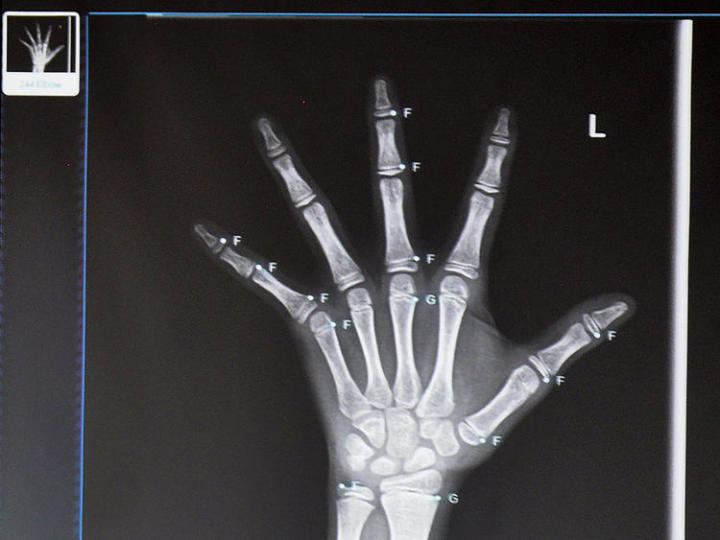

依图医疗的儿童骨龄智能诊断产品,基于医疗影像材料,通过对现有数据库的深度学习,让系统做出快速诊断供医生参考。此前医生的人工阅片,一次要耗时 10~15 分钟,这款产品将此过程缩短为数秒,诊断结果和医生人工计算的骨龄值相比,误差小于半年。

依图医疗儿童骨龄智能诊断产品示意图